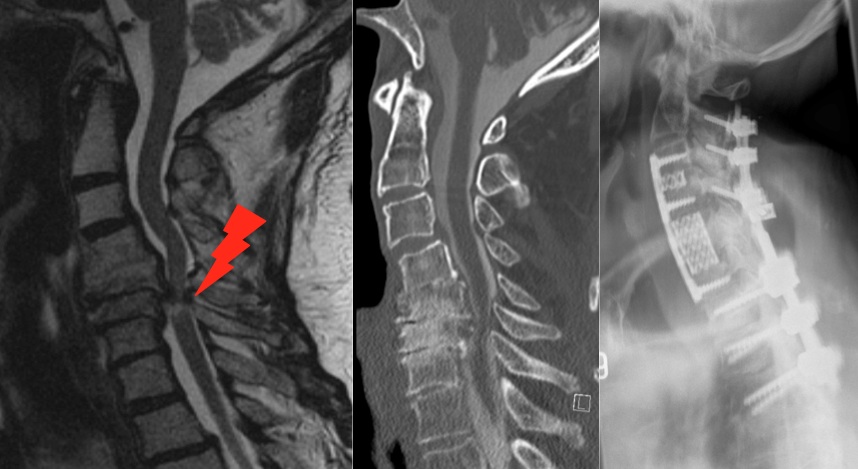

Degenerative Lumbalskoliose Wenn sich der bereits beschriebene Verschleiß in mehreren Wirbelelementen findet, kann es zu einer Verkrümmung der Wirbelsäule zur Seite hin (sog ‚Skoliose‘) kommen Normalerweise tritt eine Skoliose im Alter zwischen 10 und 12 auf. Die weitaus häufigsten degenerativen Beschwerden der Wirbelsäule finden sich im Lendenwirbelsäule (LWS) Bandscheibenvorfälle Bei Bandscheibenvorfällen (Abb 4a und 4b, MRT bei Bandscheibenvorfall LWK 3/4 rechts) wird zumeist über einen dorsalen Zugang eine mikrochirurgische Operation vorgenommen (Mikrodiscektomie). Im Laufe des Lebens kann es anlagebedingt, sowie durch allgemeinen Verschleiß zu Veränderungen der anatomischen Charakterzüge kommen, so dass die funktionellen Eigenschaften der Wirbelsäule beeinträchtigt werden Diese Veränderungen werden als degenerative Veränderungen bezeichnet.

Wirbelsaulenverletzungen Wirbelsaulenchirurgie Universitatsspital Zurich